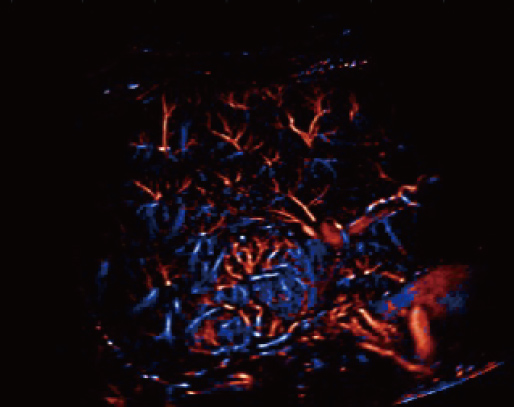

Aangestuurd door het AIT platform levert de Resona A20 een alles-in-├®├®n, ge?ntegreerde oplossing voor beeldvorming met superresolutie, iets wat voorheen moeilijk haalbaar was. SR CEUS onthult de ingewikkelde microcirculatiedetails van laesies op micronniveau, wat helpt bij onderzoeken naar microcirculatoire perfusie in oncologie.

Mogelijkheden voor microvasculaire detectie

Focale nodulaire hyperplasie | Snelheidskaart